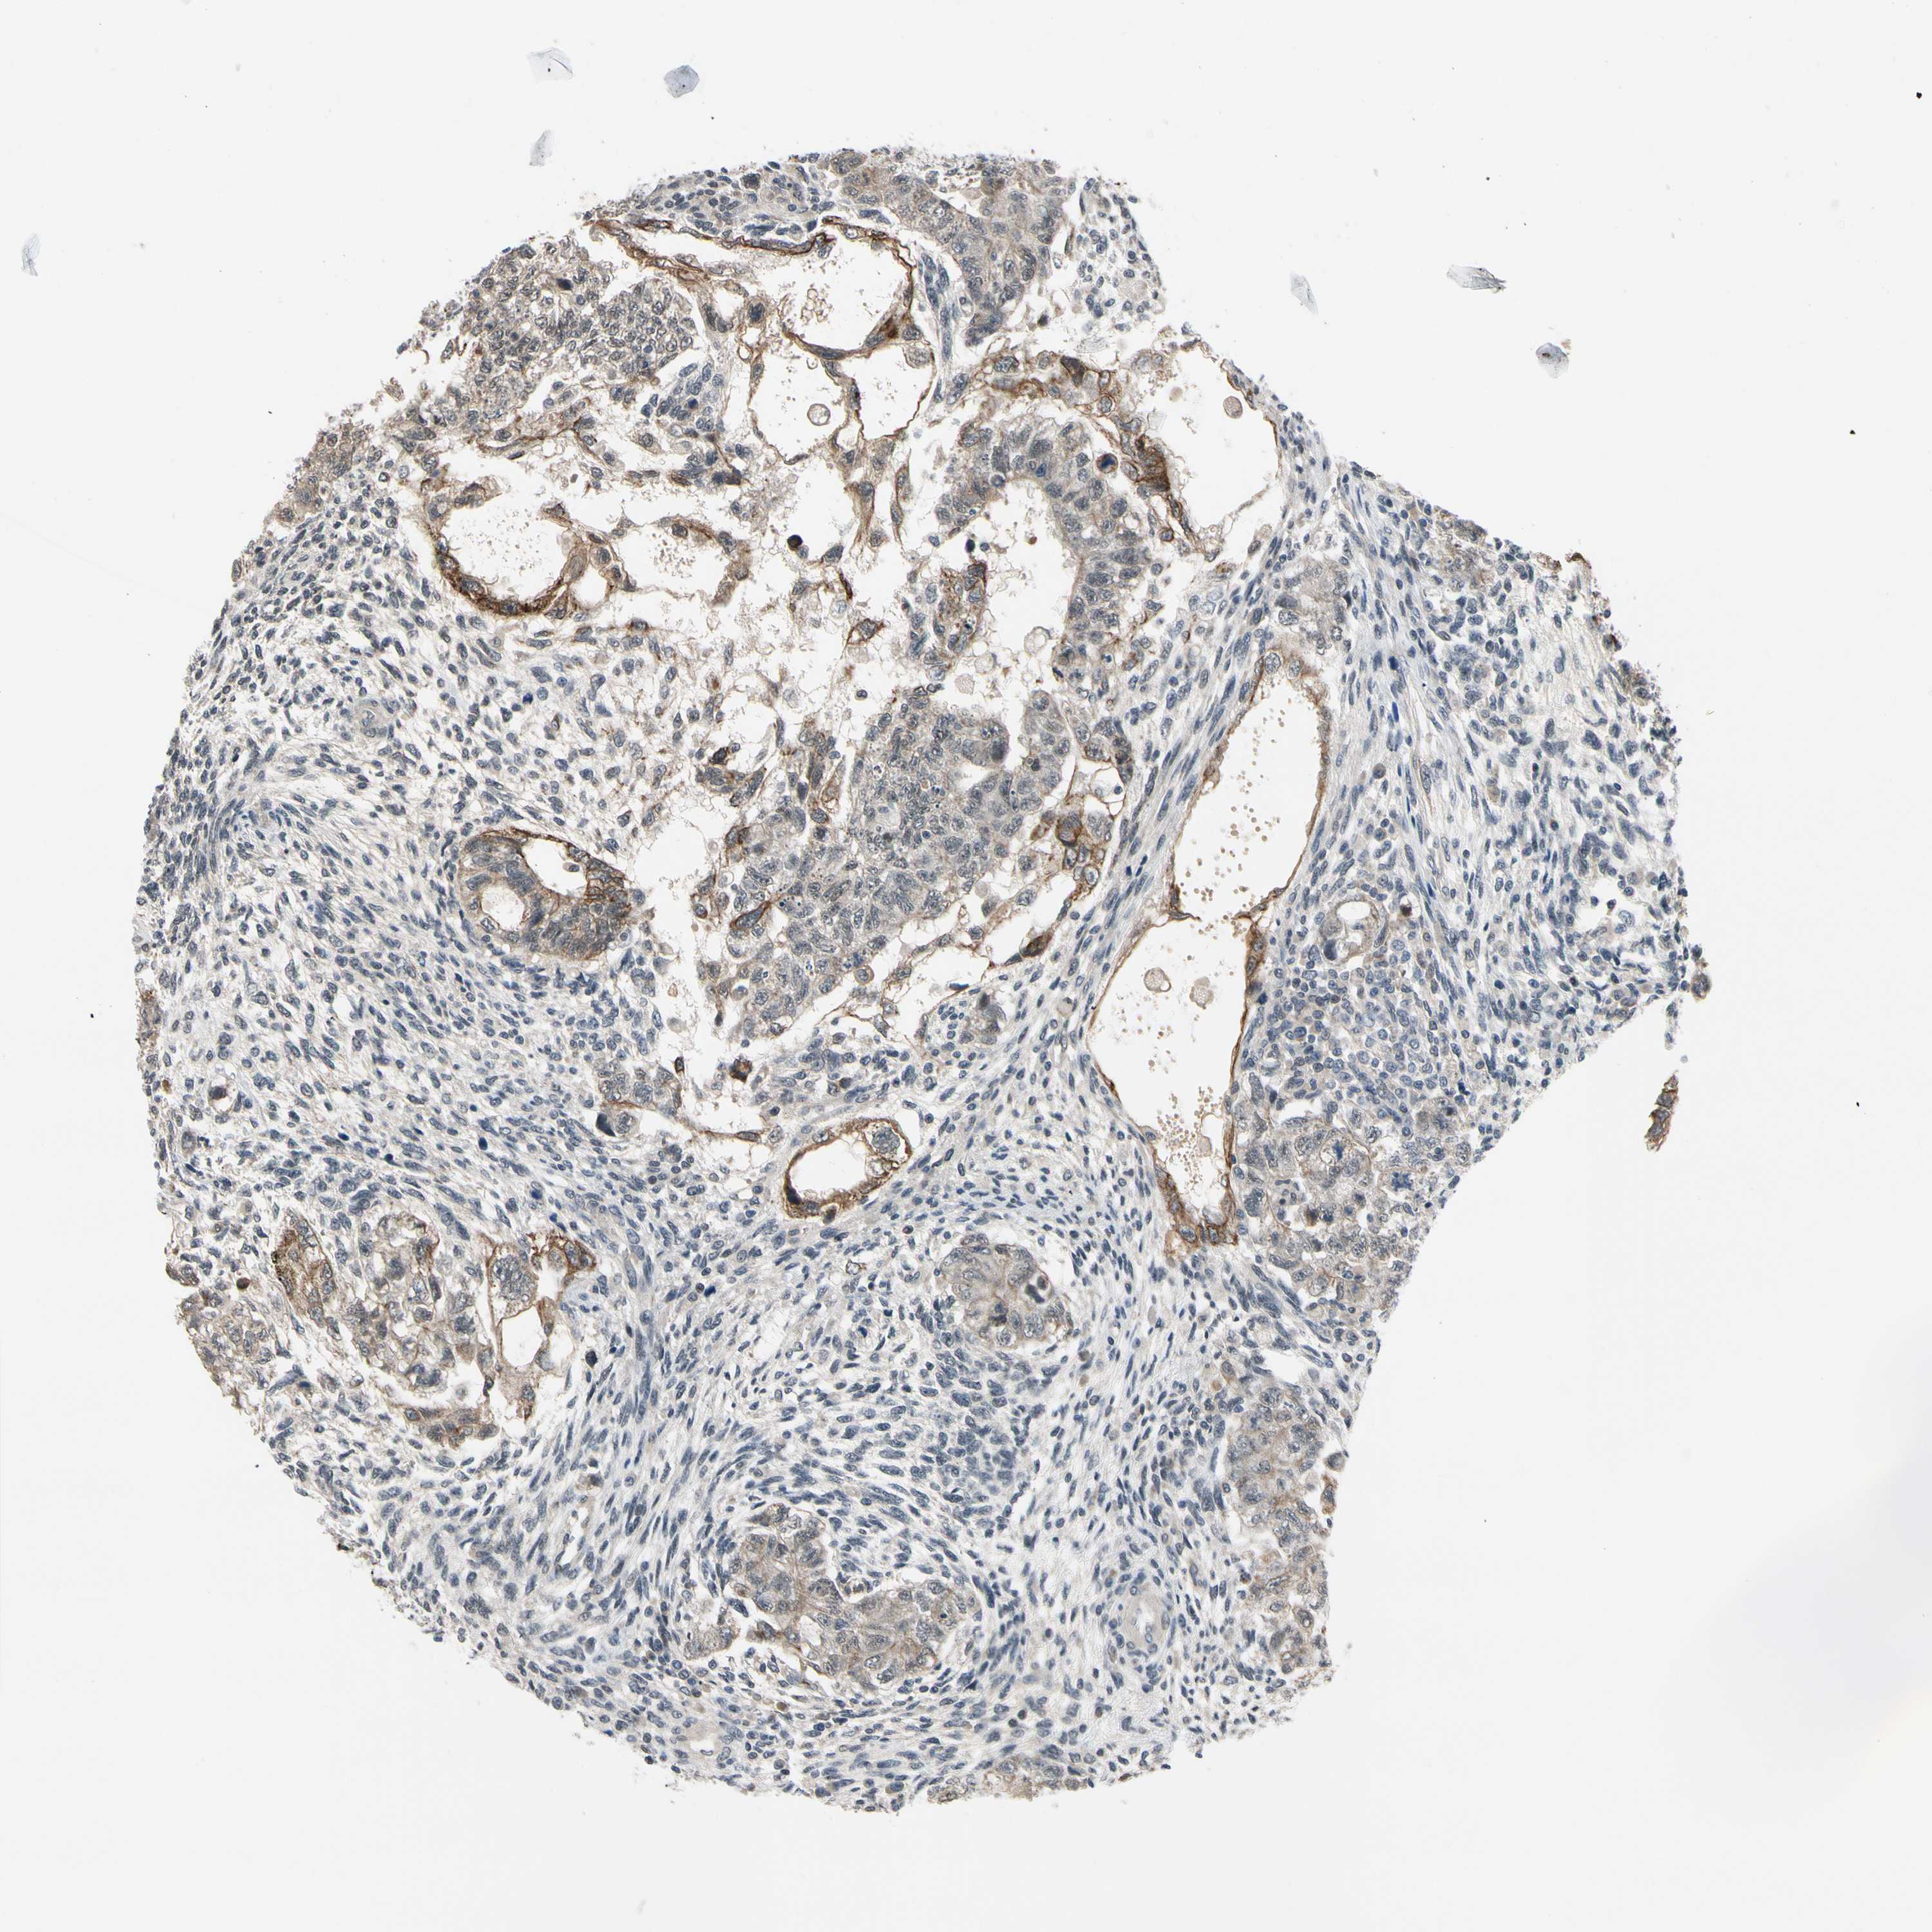

TESTIS CANCER - Protein expressioni

A mouse-over function shows sample information and annotation data. Click on an image to view it in a full screen mode. Samples can be filtered based on level of antibody staining by selecting one or several of the following categories: high, medium, low and not detected. The assay and annotation is described here.

Note that samples used for immunohistochemistry by the Human Protein Atlas do not correspond to samples in the TCGA dataset.

Antibody stainingi

Antibody staining in the annotated cell types in the current human tissue is reported as not detected, low, medium, or high, based on conventional immunohistochemistry profiling in selected tissues. This score is based on the combination of the staining intensity and fraction of stained cells.

Each image is clickable and will lead to virtual microscopy that enables deeper exploration of all samples and also displays staining intensity scores, fraction scores and subcellular localization as well as patient and tissue information for each sample.

Antibody HPA008519

Staining

High

Medium

Low

Not detected

Intensity

Strong

Moderate

Weak

Negative

Quantity

>75%

75%-25%

<25%

None

Location

Nuclear

Cytoplasmic/membranous

Cytoplasmic/membranous,nuclear

Carcinoma, Embryonal, NOS

Seminoma, NOS